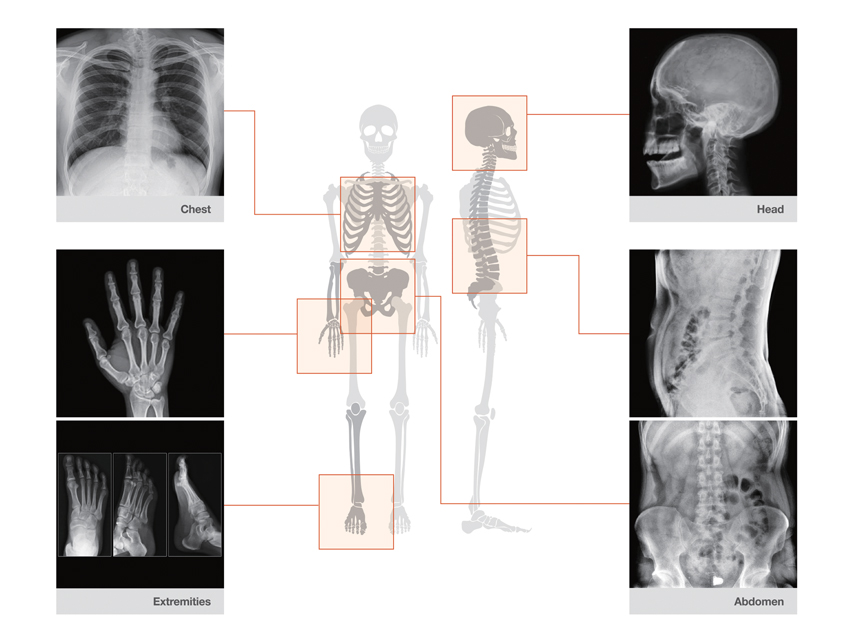

La caméra à rayons X portable REMEX KA6 est conçue pour une utilisation par des cliniciens qualifiés afin de réaliser des images diagnostiques précises du corps entier, en garantissant une exposition minimale aux radiations. Son accès rapide en fait un outil indispensable dans des environnements médicaux critiques.